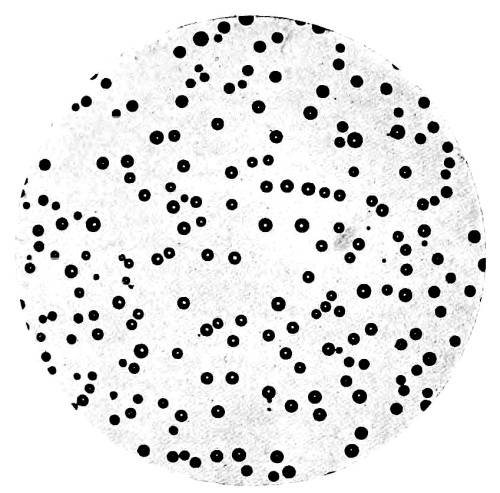

| 35. | Photo-micrograph of Globules of Mercury obtained by Reinsch‘s Process | 303 |